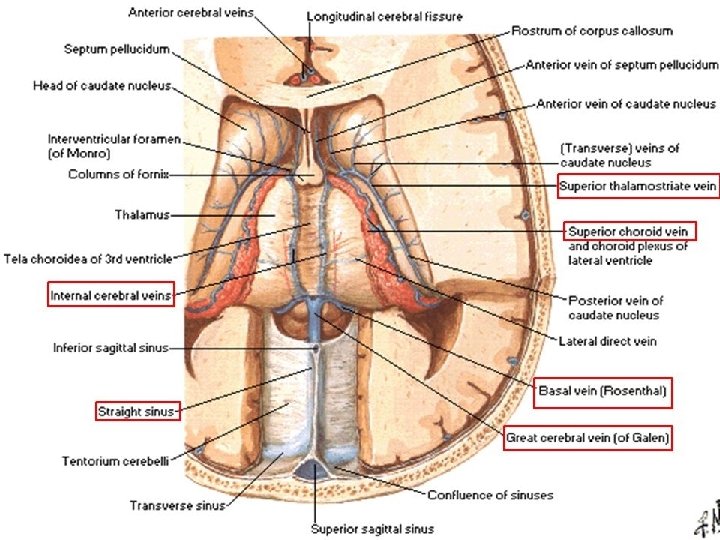

Deep Cerebral Veins • Drain deeper parts of hemispheres, basal nuclei, internal capsule, diencephalon and choroid plexus • Consists of the lateral sinuses, sigmoid sinuses, straight sinus and draining deep cerebral veins (subependymal and medullary veins) -Medullary veins are numerous and originate 1 -2 cm below cortical gray matter and pass through deep medullary white matter and drain into subependymal veins. -Subependymal veins receive medullary veins and aggregate into greater tributaries, mainly into septal veins, thalamostriate veins, internal cerebral veins, basal vein of Rosenthal and vein of Galen.

Vein Of Galen • Formed by the union of the two internal cerebral veins and basal veins of Rosenthal • Drain into the confluence of the inferior sagittal sinus and the anterior extremity of the straight sinus